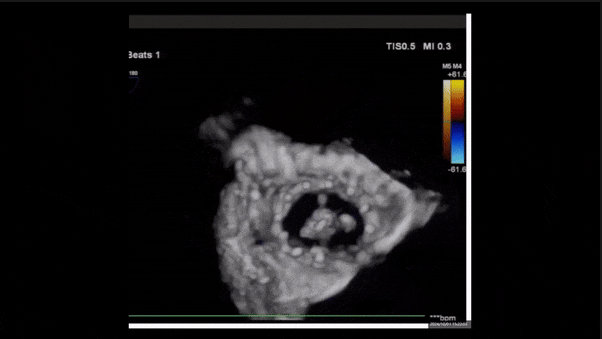

術(shù)后即刻返流三維

術(shù)后三維超聲